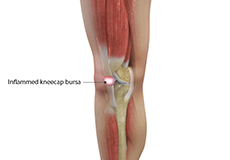

Kneecap Bursitis

Bursitis refers to the inflammation and swelling of the bursa. Inflammation of the bursa in front of the kneecap (patella) is known as kneecap bursitis or prepatellar bursitis.

Pes Anserine Bursitis

Bursitis refers to the inflammation and swelling of a bursa. A bursa is a small fluid-filled sac found between soft tissues and bones that lubricates and acts as a cushion to decrease friction between bones when they move.